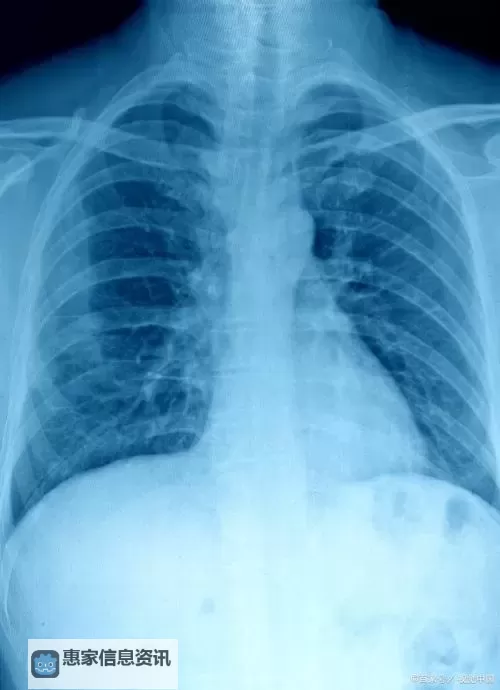

胸部X光片是一种常用且有效的疾病筛查工具,通过简单的影像检测,可以直观地观察到肺部、心脏、肋骨等部位的状况。尤其是在肺部疾病、心脏疾病等方面,胸片具有独特的优势。它不仅操作简便、费用较低,而且具有较高的检测效率,能够帮助医生快速识别潜在的健康问题,早发现、早治疗,极大地提高了疾病的治愈率。

近年来,随着医学影像技术的不断进步,胸片的曝光率和准确性得到了极大提升。所谓“100%胸片曝光率”,意味着在进行相关筛查时,几乎所有需要检测的人员都能获得完整、有效的影像资料,无遗漏,确保没有“盲点”。这对于群体健康管理尤为重要,尤其是在公共卫生事件频发的当下,大规模筛查成为控制疫情、降低疾病传播的关键措施之一。

此外,胸片的广泛应用还为慢性疾病的管理提供了便利。比如,肺部慢性阻塞性疾病(COPD)、肺纤维化、肺癌等,都可以通过定期胸片筛查进行早期发现与动态监测。这些疾病早期通常没有明显症状,但影像的细微变化可以提前提示医生采取干预措施,大大提高治疗成功率。